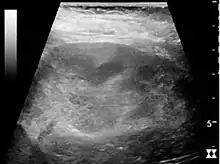

If a kidney stone is suspected (e.g. on the basis of characteristic colicky pain or the presence of a disproportionate amount of blood in the urine), a kidneys, ureters, and bladder x-ray (KUB film) may assist in identifying radioopaque stones.[9] Where available, a noncontrast helical CT scan with 5 millimeter sections is the diagnostic modality of choice in the radiographic evaluation of suspected nephrolithiasis.[16][17][18] All stones are detectable on CT scans except very rare stones composed of certain drug residues in the urine.[19] In patients with recurrent ascending urinary tract infections, it may be necessary to exclude an anatomical abnormality, such as vesicoureteral reflux or polycystic kidney disease. Investigations used in this setting include kidney ultrasonography or voiding cystourethrography.[9] CT scan or kidney ultrasonography is useful in the diagnosis of xanthogranulomatous pyelonephritis; serial imaging may be useful for differentiating this condition from kidney cancer.[10]

Ultrasound findings that indicate pyelonephritis are enlargement of the kidney, edema in the renal sinus or parenchyma, bleeding, loss of corticomedullary differentiation, abscess formation, or an areas of poor blood flow on doppler ultrasound.[21] However, ultrasound findings are seen in only 20% to 24% of people with pyelonephritis.[21]